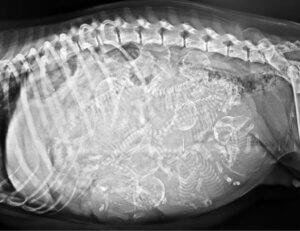

As surprising as it may seem, the story of this dog isn’t unique in the animal kingdom. Cyclopia is a major congenital malformation that occurs in many animals, characterized by the presence of a central eye resulting from the fusion of the 2 eyes and alobar holoprosencephaly —the failure to develop cerebral hemispheres.